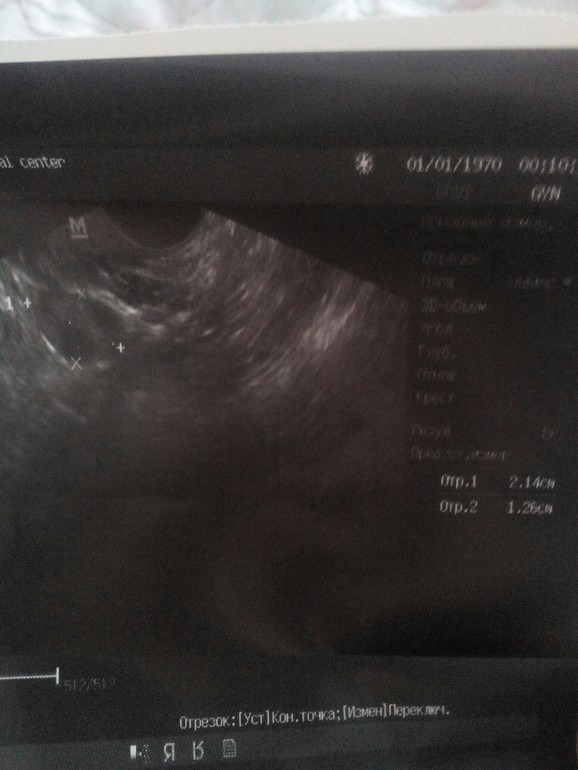

Сегодня 12дц не выдержала и сходила гляеуть в закрома своего тела) в платную клинику

Вот только интересно будет от овуля?? Хоть эндик в этом цикле не такой крошечный как в том) витаминки работают))

Я вот фотуи смотрю и не знаю где там этот эндометрий) может кто разбирается, там точно не эндометрита? Меня уверяла прошлая узистка что есть и сильный, простите может я уже свистануиая но хочется 100 раз услышать что все хорошо и верить в это)

Эндик 0.91см-трёхслойный как положенно в первой фазе,а вот фоллики не поняла все 6-8 до 1,5см??Или их 6-8 и один из низ домминант 1,5?Нужно в таких случаях у них уточнять

ДФ - 1,5 см, М эхо - это и есть эндометрий, норм для такого размера фолика, все в порядке, О будет через 3-4 дня